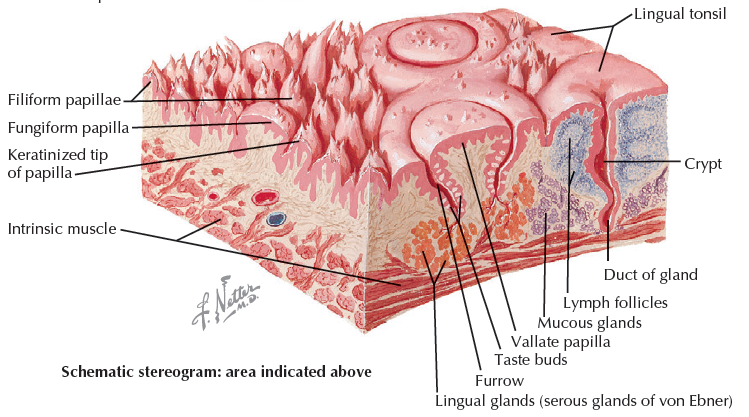

舌頭

Structure

- Terminal sulcus(terminalis)分前後

Papillae

Filiform

- 最多

- 無 taste buds

Fungiform

- 前側

- CN VII

Foliate

Circumvallate

- 後側

- CN IX

Nerve

運動

感覺

- 根部 taste/ general sense

- 後 taste/ general sense

- 前

- Taste: Chorda tympanic

- General sense: Lingual n

Hyoglossus m. 外側

- Lingual n.

- Hypoglossal n.

- Submandibular duct